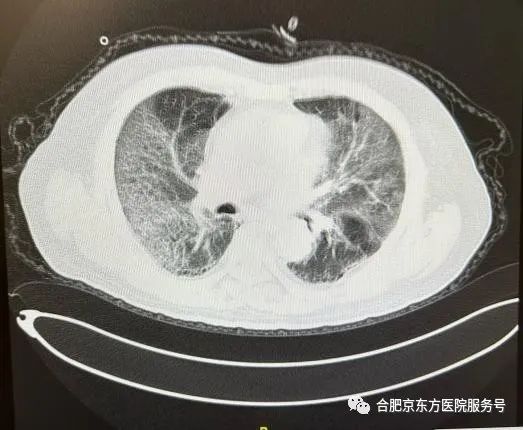

「当时患者新冠肺炎合并呼吸衰竭,情况比较危险,血氧饱和度只有 70-80,肺部 CT 有白色阴影。」

当天晚上,王老伯从急诊转入呼吸内科住院治疗。但此时病情发展仍十分迅速,喘憋逐渐加重,平静状态下都会呼吸窘迫,就连晚上睡觉也无法躺平,只能坐着休息。三天后复查 CT 的结果,也着实让大家捏了一把冷汗,因为此时王老伯的肺部 CT 表现就是俗称的「大白肺」。

「王老伯自己挺给力,家属也非常配合。」舒冬冬医师表示,相关治疗手段用上之后,王老伯的情况在持续改善。血氧指标一步步回升到 95% 以上,复查胸部 CT 提示白肺较前明显吸收好转。